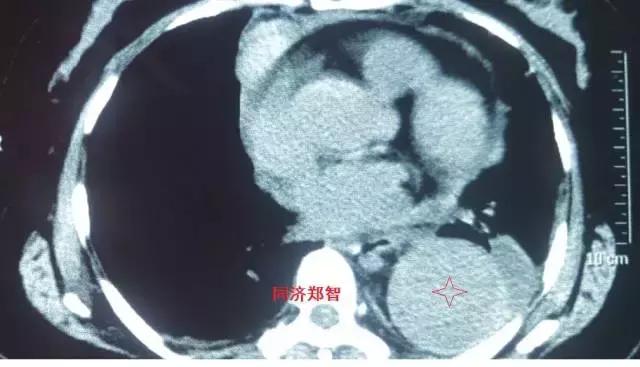

第一招 血管直径增大征

这个征象比较好识别,当主动脉夹层形成巨大的夹层动脉瘤时,通过胸片、平扫CT、彩超等也能初步诊断主动脉病变。

病例四

腹部平扫CT提示腹主动脉增宽,CTA证实为腹主动脉局限性夹层(红箭头所示)。